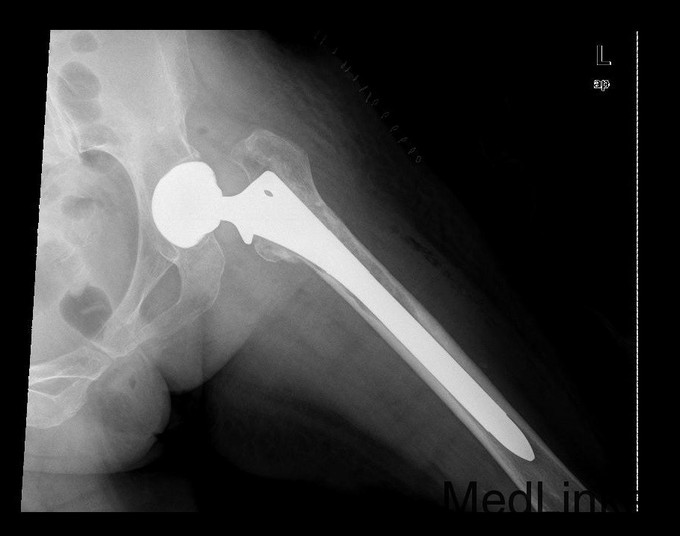

查体:专科:左髋部后外侧陈旧手术瘢痕,左髋关节前方压痛、无轴向叩击痛阴性,无大转子叩击痛,双下肢感觉及血运均正常。双下肢肌力V级。动量:右髋内外旋诱发疼痛,屈曲90度疼痛。外旋明显滚动试验阴性,左髋4字试验阳性。双下肢等长。左髋关节屈90°,伸0°,外展40°,内收20°,内旋30°外旋10°。右髋关节屈120°,伸直0°,外展40°,内收20°,内旋30°外旋30°。 辅助检查:2010-12-08 ESR 6.0mm/h,2011-01-04外院CRP8.5mg/l(参考范围0-10mg/l)X线示左双动股骨头置换术后,假体松动、下沉,髓腔内可见骨水泥影。近端干骺端骨质明显缺损。髓腔内侧皮质形态不规则。

诊断:左双动股骨头置换术后假体松动、下沉、股骨骨缺损(PaproskyII型) 治疗:患者在全麻下左双动股骨头假体取出+同种异体骨植骨+左全髋关节翻修术,术后予以抗炎(二联)+抗凝+镇痛+护胃+补液等治疗,并予以抗骨质疏松药物

出院时左髋可屈曲90°,伸直0°,外展30° 讨论: 1、髋臼侧是否置换关键看什么? 2、Paprosky分型? 3、高龄患者行骨科大手术围手术期应着重注意哪些方面?( 体力、肺部感染、液体量与心功能、营养与饮食、锻炼与下肢深静脉血栓~~~~~) 4、假体柄的选择有何要求? 5、术后1天与术后3月的片子有何差别,试分析原因